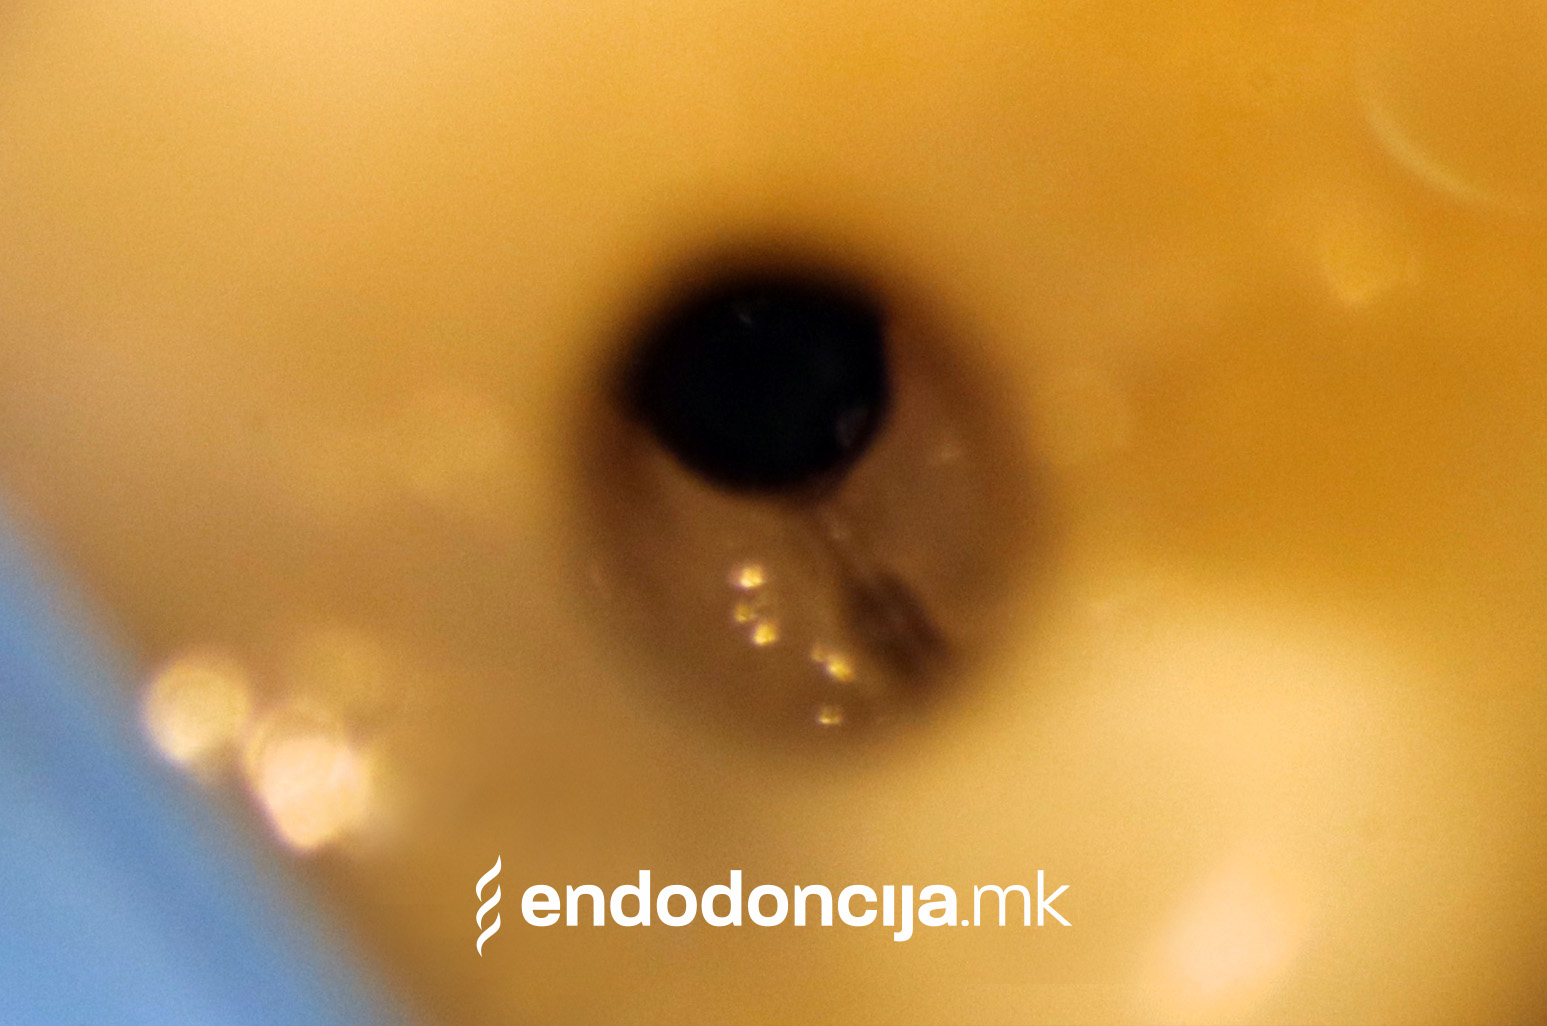

Она што е импресивно е прецизноста на микроскопските третмани. Дури и кога каналите се потешко достапни, може да се лоцираат и исчистат така што релапсите се со помала веројатност. Спротивно на тоа, скриените канали често остануваат неоткриени во конвенционалниот третман на коренскиот канал и затоа не можат да се чистат. Бактериите можат да се размножуваат таму без пречки и да предизвикаат воспаленија. Ова често останува незабележано со години додека не се појави забоболка, а со тоа и компликации.

Употребата на микроскоп исто така овозможува детектирање пукнатини или фрактури што може да предизвикаат болка или воспаление.